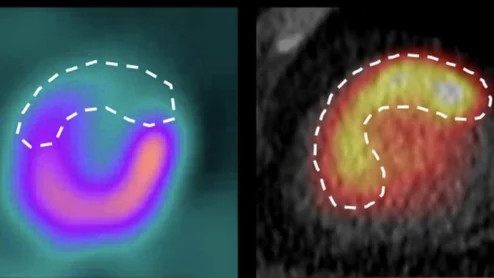

American Society of Echocardiography (ASE) President David H. Wiener, MD, FACC, FAHA, FASE, director of clinical operations at the Jefferson Heart Institute, and a clinical professor of medicine at Thomas Jefferson University, explains the growing number of multimodality cardiac imaging experts and how imaging societies need to change to meet their needs.

ASE President David Wiener detailed some of the many ways imaging societies need to adapt now that so many imagers are specializing in multiple modalities. It may be time to change how annual conferences are scheduled, for example, so that the costs of travel are easier to manage.